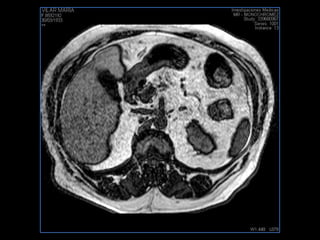

PROTOCOLO abdomen COR T2, AXIAL supresion grasa AX T1 +SAG T2  CON   GADOLINIO :  COR T1+AX T1(DIN) SAT: NO  FASE: RL THK: 6MM  COIL:  GAP: (FACTOR 1.4) 2MM FOV: 40 CM NEX:2 SINCRONIZACION RESPIRATORIA EN 3 O 4 CICLOS ALE

resonancia de abdomen